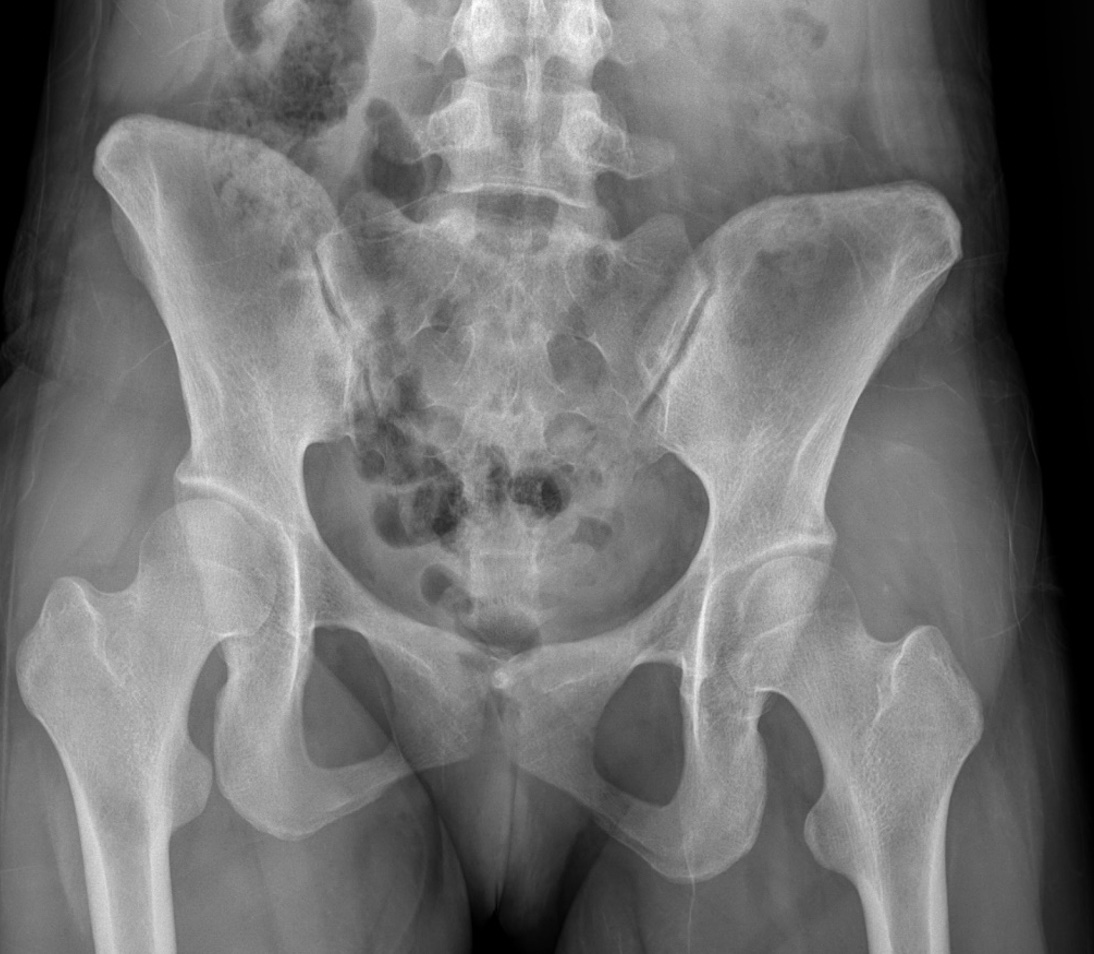

gout arthritis ( rid3567 )